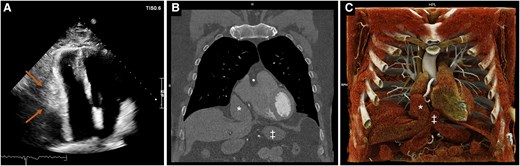

πŸ“’ New Image Focus #EHJCVI A rare incidental finding of liver herniation into the pericardium πŸ«€ https://t.co/T4EC4aP2dG Very proud of this young promising CV imager @inesmarodriguesπŸ‘ΈπŸ» who I was happy to mentor in her first #echofirst πŸ‘£πŸ‘£ #EACVI #HIT @EHJCVIEiC @EACVIPresident

Congenital left pericardial agenesis with pulmonary vein stenosis: multimodality imaging insights by @EHJCVIEiC πŸ‘‰ https://t.co/WEiXN31xdu 39M with chest pain. CT: absent left pericardium β†’ LV shift & L inf. PV stenosis (β€œSnoopy Nose Sign”). Conservative care; well at 3 mo.